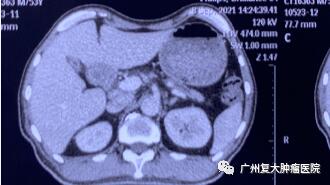

图3

为减轻肿瘤负荷,改善生活质量,延长患者生命,经患者及家属同意,我院牛立志院长为其实行胰腺肿瘤、肝脏肿瘤不可逆电穿孔治疗,术中以胰腺肿瘤、肝脏10个病灶为靶区消融。术后联合化疗加免疫药物治疗进一步改善治疗效果。

术后一周检查发现,身体各项指标逐步恢复正常。与之前相比,上腹部MRI图像提示胰腺、肝脏肿瘤中心大部分坏死。术后一年复查显示,肿瘤缩小,得到较好的控制。